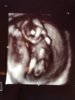

Wow spennandesHer er våre to små 8+4. Verdens fineste overraskelse. Den ene er 1,75 cm og den andre er 1,55cm. To bankende hjerter og begge bevegde seg![]()

![]()